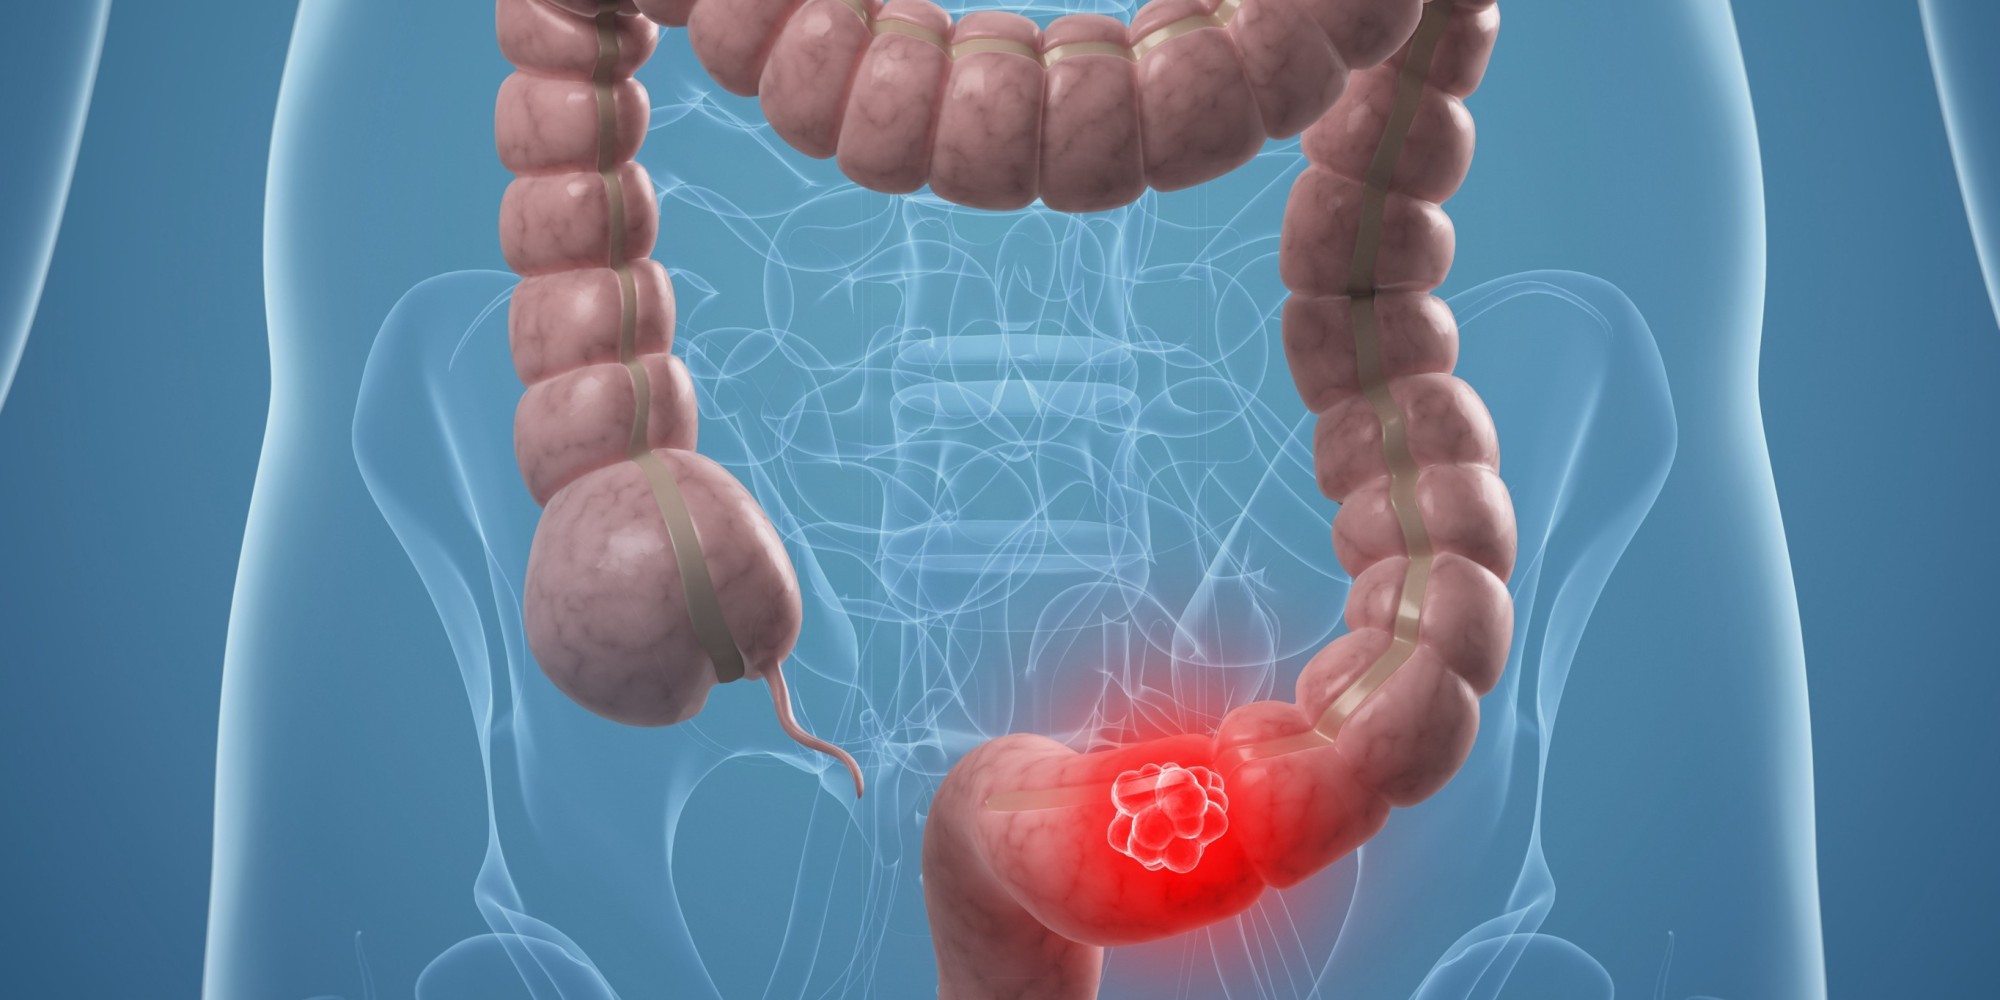

Σχεδόν το 5,2%των καρκίνων που διαγνώστηκαν το 2015 θα μπορούσε να είχε αποφευχθεί με καλύτερη διατροφή. Αυτό δείχνει έρευνα που δημοσιεύθηκε στο JNCI Cancer Spectrum η οποία υπολογίζει τον αριθμό, το ποσοστό και τον τύπο συγκεκριμένων καρκίνων οι οποίοι οφείλονται στην υπερκατανάλωση τροφών και ροφημάτων με πρόσθετη ζάχαρη.

Στη μελέτη εκτιμάται πως 80.110 νέες περιπτώσεις επιθετικού καρκίνου στις ΗΠΑ το 2015 οφείλονταν στις κακές διατροφικές επιλογές.

Πρόκειται για ένα ποσοστό το οποίο είναι συγκρίσιμο και σχεδόν στα ίδια επίπεδα με τον καρκίνο που προκύπτει από την κατανάλωση αλκοόλ ο οποίος κυμαίνεται μεταξύ του 4-6%.

«Τα ευρήματά μας υπογραμμίζουν την ευκαιρία να μειωθούν τα περιστατικά καρκίνου μέσω της βελτίωσης των τροφών που καταναλώνουμε», αναφέρει ο πρώτος συγγραφέας της έρευνας, Fang Fang Zhang.

Η αναφορά των ερευνητών σημειώνει ότι υπάρχουν πειστικά στοιχεία και ενδείξεις ότι μια διατροφή με υψηλή πρόσληψη επεξεργασμένου ή κόκκινου κρέατος και χαμηλή σε δημητριακά ολικής άλεσης, γαλακτοκομικά, φρούτα και λαχανικά αυξάνει τον κίνδυνο για καρκίνο του στόματος, του φάρυγγα και του λάρυγγα, ενώ η κατανάλωση επεξεργασμένου κρέατος αυξάνει επίσης τον κίνδυνο για καρκίνο του στομάχου.

Οι ερευνητές μελέτησαν επίσης ζαχαρούχα ροφήματα λόγω των ήδη γνωστών συσχετισμών τους με την παχυσαρκία και 13 τύπους καρκίνου.

Τα κυριότερα ευρήματα της έρευνας αναφέρουν ότι:

Ο καρκίνος του παχέος εντέρου είχε το μεγαλύτερο ποσοστό καρκίνων που σχετίζονται με τη διατροφή φτάνοντας το 38,3% όλων των περιπτώσεων του 2015 που σχετίζονταν με τη διατροφή.

Η πρόσληψη δημητριακών ολικής άλεσης σε χαμηλά επίπεδα είχε συσχετιστεί με το μεγαλύτερο αριθμό και ποσοστό νέων περιπτώσεων καρκίνου, ενώ ακολουθήθηκε από τη χαμηλή πρόσληψη γαλακτοκομικών, την υψηλή κατανάλωση επεξεργασμένου κρέατος, τη χαμηλή πρόσληψη φρούτων και λαχανικών, την υψηλή πρόσληψη κόκκινου κρέατος και τέλος την υψηλή κατανάλωση ζαχαρούχων ροφημάτων.

Ο μεγαλύτερος αριθμός των περιστατικών καρκίνου που σχετίζονταν με την κακή διατροφή αφορούσε καρκίνο του παχέος εντέρου με 52.225 περιστατικά. Ακολουθήθηκε από καρκίνους του στόματος, του φάρυγγα και του λάρυγγα (14.421), καρκίνο της μήτρας (3.165), καρκίνο του μαστού (3.059), καρκίνο στους νεφρούς (2.017), καρκίνο του στομάχου (1.564) και καρκίνο του ήπατος (1.000).

Από τις περιπτώσεις καρκίνου που σχετίζονταν με τη διατροφή, σχεδόν το 16% αποδίδονταν και στην παχυσαρκία.